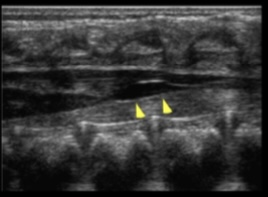

What is demonstrated on the spine image?

filar cyst